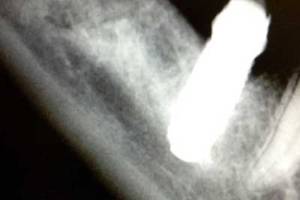

Dolor a la hemimandíbula dreta causat per un implant massa proper al nervi dentari inferior dret, que li provocava una nevralgia del trigemin.

Explantació de la fixació dental 4.6 amb molt de compte per no intruir més l’implant ni perjudicar més el nervi.